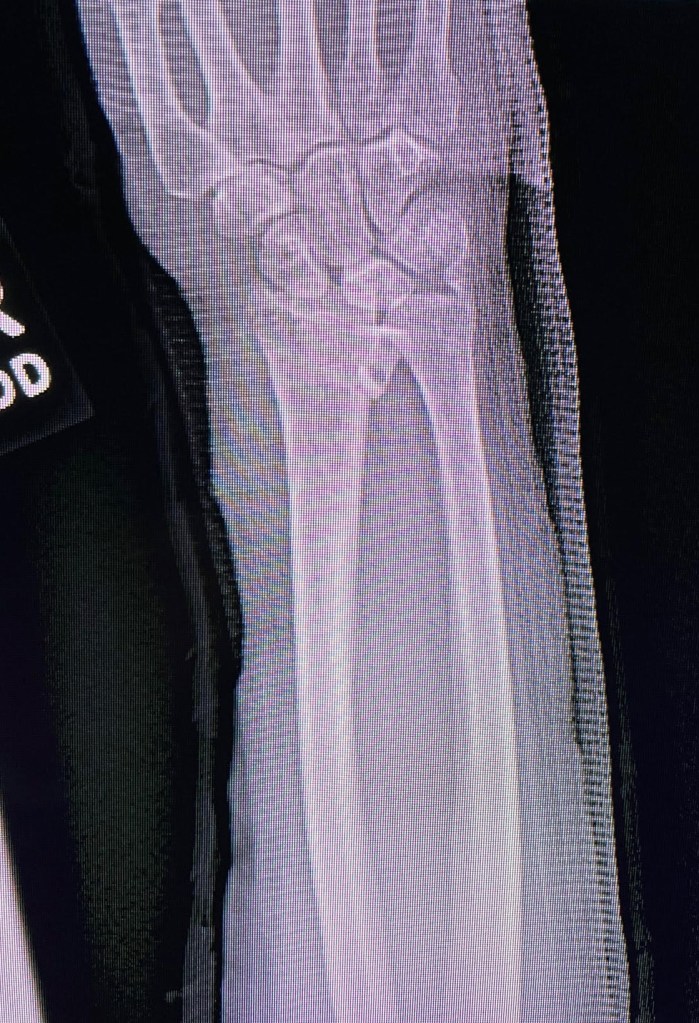

Could it be, this personal neglect of our mother’s body rebounded against our own? For at the end of June in Boston, where I’d come to collect what things she’d left, I fell and broke my right wrist on a pickleball court about three minutes into my first lesson. Surprised out of a lucky and relatively doctor-free lifestyle, my body had to breast a flash flood of x-rays and forms and consultations and administrations of surgical drugs; a piece of metal was installed. Getting its bone density checked just lately by a radiologist, my body was lying flat on an exam table while a curious remote-operated contraption devoured the secrets of its insides from above. Meanwhile, my sister broke a tooth and had to get a crown: a summer, this, to be remembered as the one when our bodies reenacted our mother’s body’s final helpless consignment to the hands of competent strangers.